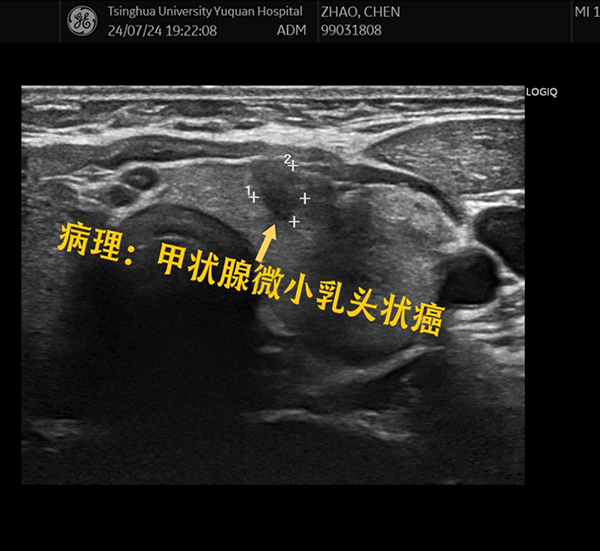

近期,一位来自河北保定的中年男性患者,通过了解超声诊断科卜云芸主任团队的科普视频,来我院就诊。该患者自述2年前因为生气,脖子上突然长出一个大包,去医院检查发现甲状腺内有一个囊实性结节,大小约2cm左右,一直未在意,直到现在结节越长越大,已经有明显的压迫感,并且影响吞咽和呼吸,于是四处求医,先后在当地市医院、北京其他三甲医院进行了对比、斟酌,最后决定来我院就诊。

卜云芸主任团队为该患者进行了详细的术前评估,这是一个以囊性为主的囊实性结节,最大直径已达7.3cm,在充分告知患者手术切除和超声引导下微创消融各自的优缺点后,患者主动选择超声引导下微创消融治疗。

消融前